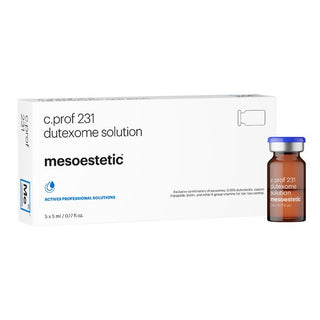

meso.prof

ACTIVES PROFESSIONAL SOLUTIONS

transepidermal solutions by mesoestetic®

meso.prof is the widest range of solutions for transepidermal application for performing combinable, safe, effective cosmetic treatments. Formulations with specific, selected active ingredients for the purpose of treating all types of aesthetic facial, body and hair concerns.